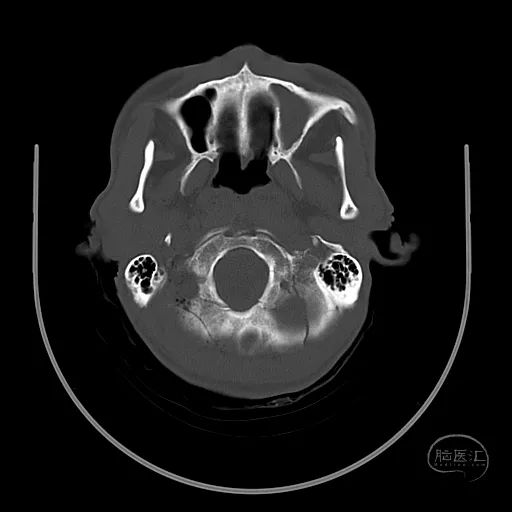

患者,男,53岁,因车祸伤1小时来诊,入院时患者烦躁,GCS评分5分,不能对答,双侧瞳孔等大等圆,直径2mm,对光反射迟钝,四肢躁动,自主呼吸尚稳定。

颅脑CT可见左侧小脑半球挫裂伤,第四脑室明显受压。

右额叶脑挫裂伤并血肿,侧脑室额角受压,脑室无明显扩张。

中线结构稍向左侧偏移。

骨窗显示枕骨粉碎性骨折,累及枕骨大孔左侧,齿突尚居中。